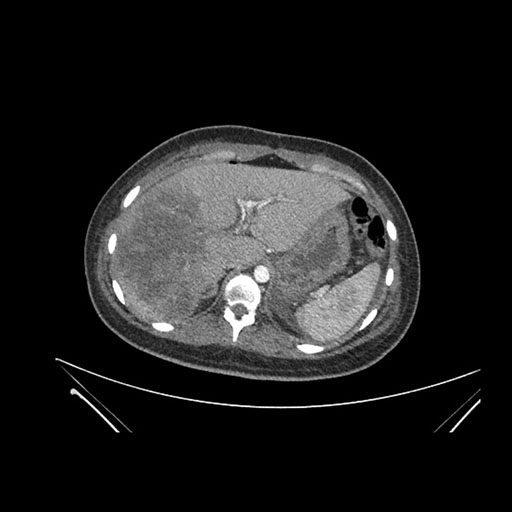

Vasculobiliary injury [M28]

Imaging Analysis

Look through the patient's CT scan to identify any areas of concern for the necessary procedure.

Axial Arterial